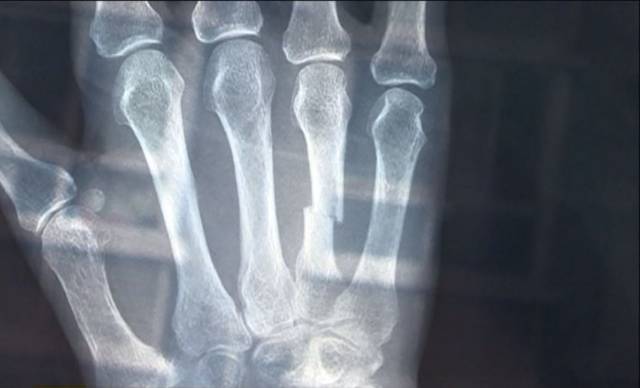

老人是左手第4掌骨骨折